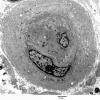

Hypoxia-Ischemia, fetal-neonatal

White Matter (4)